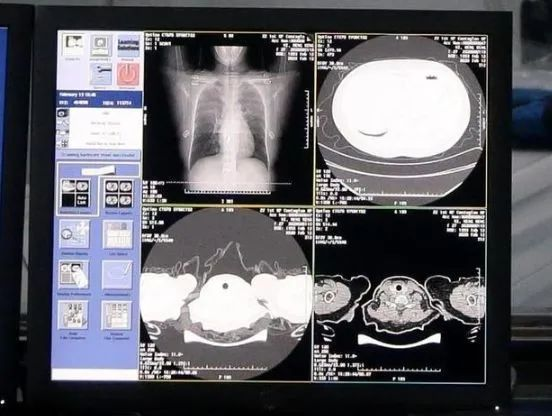

另外,根据浙江省疾控中心的报告,新型冠状病毒是基因组序列最长的病毒之一,用常规方法快速检测基因组全貌非常困难,而临床的诊断却要在基因信息的基础上进行。

而阿里达摩院的AI算法,是基于当前最新的诊疗方案、钟南山等多个权威团队发表的关于新冠肺炎患者临床特征的论文,突破了训练数据不足的局限,基于5000多个病例的CT影像样本数据,学习训练样本的病灶纹理而研发建立的。

算法可将3-4小时的分析流程缩短到半小时,因此医生可以尽快掌握病毒是否有变异、以及特征,为防控、治疗提供更多依据。

同时阿里达摩院也宣布向科研机构免费开放阿里云超算系统的全部算力,在基因诊断、药物筛选上的速度会比常规手段更快。

AI算法和5G新应用

根据浙江省疾控中心的报告,新型冠状病毒是基因组序列最长的病毒之一,用常规方法快速检测基因组全貌非常困难,而临床的诊断却要在基因信息的基础上进行。

而阿里达摩院的AI算法,是基于当前最新的诊疗方案、钟南山等多个权威团队发表的关于新冠肺炎患者临床特征的论文,突破了训练数据不足的局限,基于5000多个病例的CT影像样本数据,学习训练样本的病灶纹理而研发建立的。

算法可将3-4小时的分析流程缩短到半小时,因此医生可以尽快掌握病毒是否有变异、以及特征,为防控、治疗提供更多依据。

同时阿里达摩院也宣布向科研机构免费开放阿里云超算系统的全部算力,在基因诊断、药物筛选上的速度会比常规手段更快。